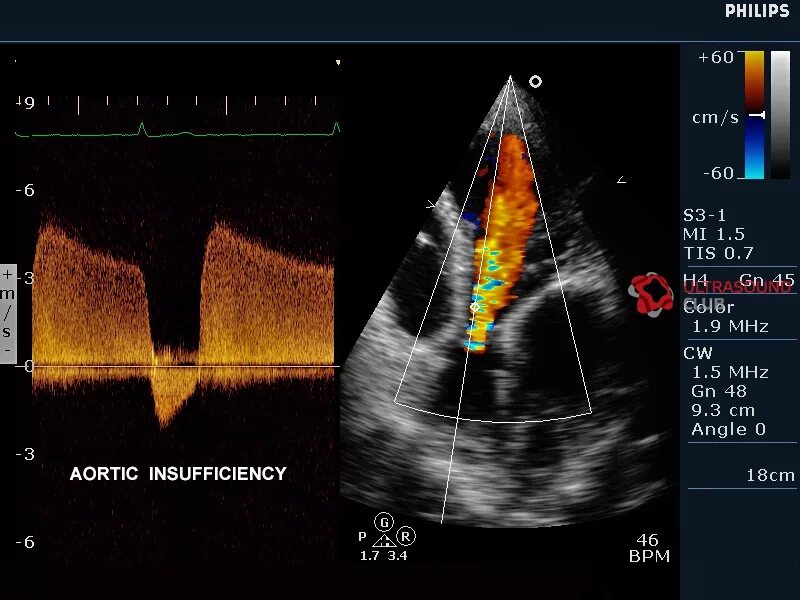

Узи сердца показывает сердечную недостаточность